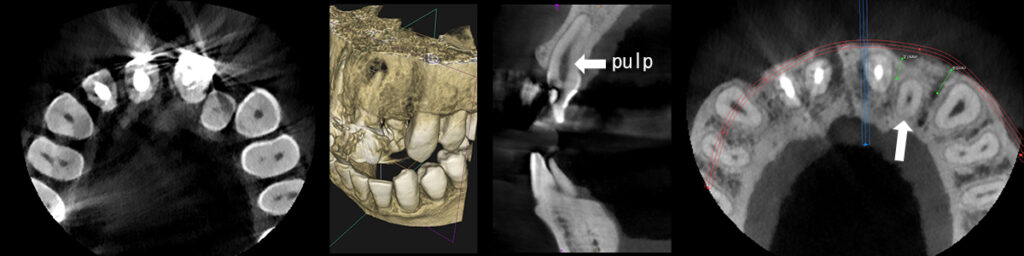

CT撮影により歯根の近接具合の確認とアンカースクリューの設置位置の確認